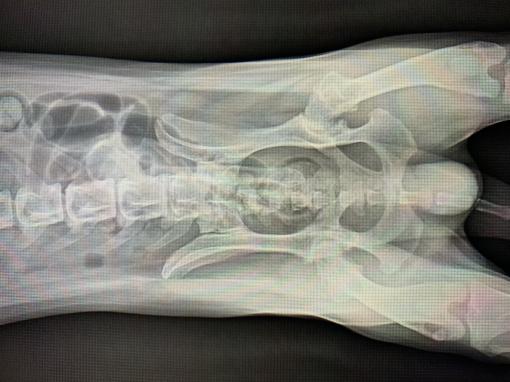

跟醫生形容後拍了X光

醫生說明他是後髖關節處退化了

增生了一些軟骨組織導致他動作時會與骨頭相互摩擦而不舒服。